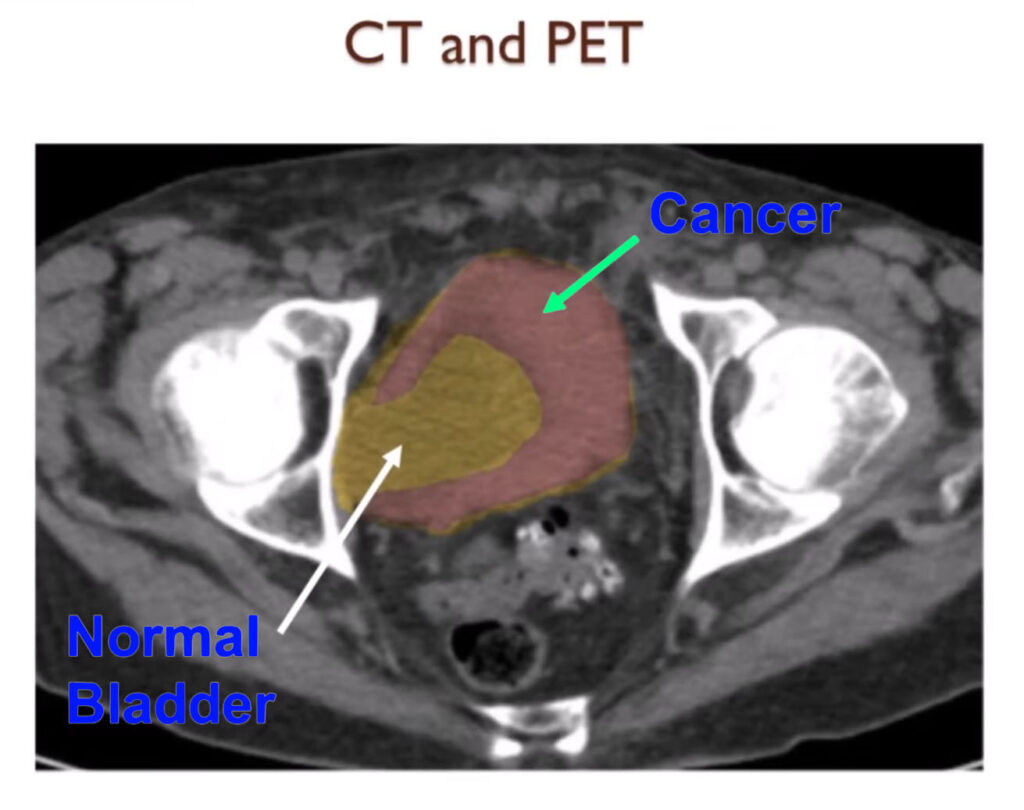

CT and PET

PET scans may not be as helpful with bladder cancer as you might otherwise think.

Here’s a CT scan and you can see the tumor in the wall of the bladder colored in red.

But when we did the PET CT scan the inside of the bladder the urine lights up on the PET scan and actually makes it hard to see the cancer. PET scans are good however to show if the cancer is spread elsewhere in the body.